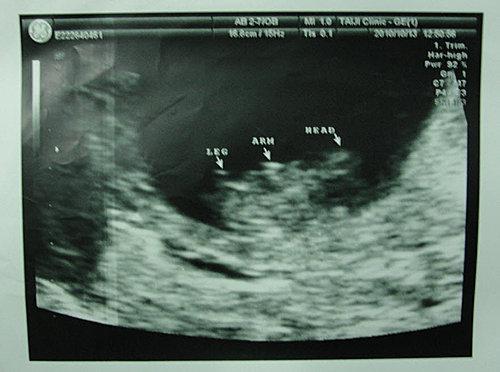

At the date of pregnancy test, I finally saw the two lines in the pregnancy test kit, and I could help but pleasantly surprised. My husband even looked at the two lines in the pregnancy test kit for over 20 minutes. With the help of Dr. Chang’s, we realized our baby dream.